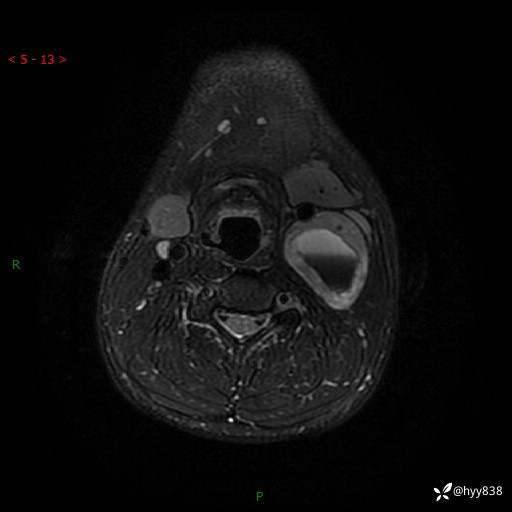

年轻小伙,发现左侧颈部肿物3年余,逐渐增大---结果公布~

现病史:患者约3年前因感冒发现左侧颈部长一肿物,约半个鸡蛋大小,无明显疼痛及其他不适,一直未行特殊处理。3个月前发现左侧颈部肿物变大,随后至当地市第二人民医院耳鼻喉科行左侧颈部彩超示:左侧颈部囊实混合性包块;喉部MPR示:左侧胸锁乳突肌内前方占位,累及左侧喉旁间隙,建议增强扫描。建议手术治疗。患者考虑。随后至我院肿瘤科就诊,行细胞学穿刺示:考虑血管源性肿瘤可能,建议进一步检查。建议至我院口腔科就诊,行颌面部MRI示:左侧颌下腺后方团状异常信号灶,建议增强。建议手术治疗。为求进一步治疗,门诊以“左侧颈部肿物”收入院。 起病以来,患者神志清、精神良好,饮食睡眠良好,大小便正常,体重未见明显变化。

颈部MRI平扫+增强